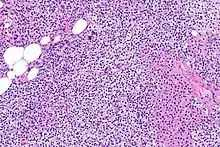

Hyperparathyroidism, in general, is caused by either tumorous growth in one or more parathyroid glands or a prolonged decrease in blood calcium levels or hypocalcaemia which in turn stimulates the production of parathyroid hormone release from the parathyroid gland.[10][11] The parathyroid gland is located beside the thyroid gland in the neck, below and in front of the larynx and above the trachea. It is composed of four glands in total that monitor blood calcium levels via the calcium sensing receptors, a g-coupled protein receptor.[12] The parathyroid glands main role is calcium homeostasis.[13][12] Histologically, these glands are composed of chief cells and oxyphil cells with the chief cell primarily responsible for the storing and release of parathyroid hormone. These cells are arranged in a pseudo-follicular pattern similar to the thyroid follicles. Keratin staining is used to image the parathyroid hormone granules.[9][14]

Parathyroid glands are normally composed of chief cells, adipocytes and scattered oxyphil cells.[27][14] Chief cells are thought to be responsible for the production, storage and secretion of parathyroid hormone. These cells appear light and dark with a prominent Golgi body and endoplasmic reticulum. In electron micrographs, secretory vesicles can be seen in and around the Golgi and at the cell membrane. These cells also contain prominent cytoplasmic adipose.[27][14] Upon onset of hyperplasia these cells are described as having a nodular pattern with enlargement of protein synthesis machinery such as the endoplasmic reticulum and Golgi. Increased secretory vesicles are seen and decreased intercellular fat is characteristic.[27][24] Oxyphil cells also appear hyperplasic however, these cells are much less prominent.